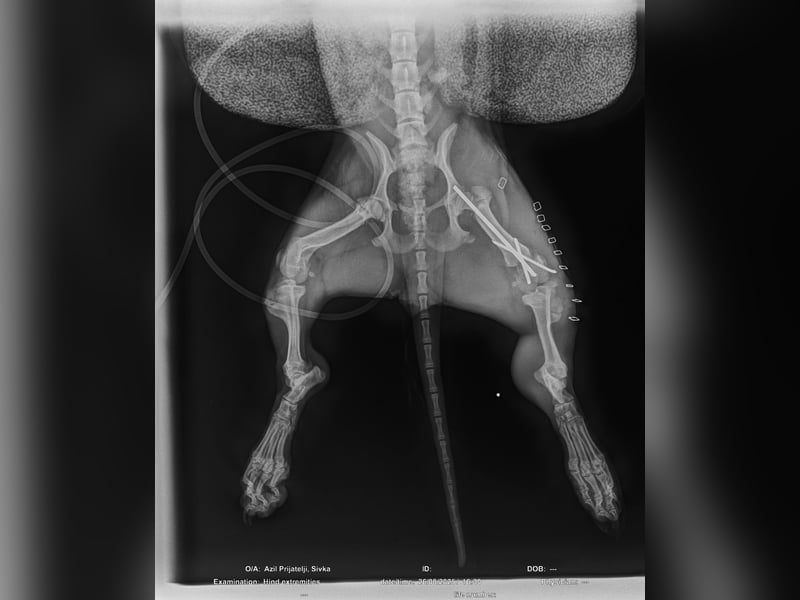

Ilse hatte einmal eine Besitzerin, doch ihr Leben war nicht leicht. Als sie aus dem Hof entkam, wurde sie von einem Auto angefahren und brach sich ein Bein. Zum Glück konnte sie operiert werden – die OP war erfolgreich, und Ilse läuft und rennt wieder ganz normal! Die Metallstifte werden in Kürze entfernt.